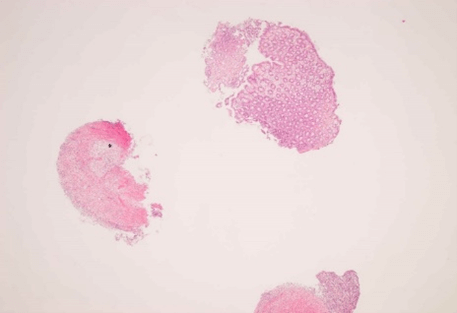

Figure 5: Descending colon (x2).

Asterisk: Fragments of inflammatory material, Arrow: Mucosal surface ulceration.

Figure 7: Splenic flexure (x2).

Asterisk: Fibroinflammatory material.

The histology showed fragments of fibroinflammatory material along with some normal large intestinal mucosa. In other areas, the crypts were atrophic and withered in appearance with hyalinisation of the lamina propria and variable oedema. There was surface ulceration in the descending colon. Residual crypts contained acute inflammatory debris, and there was mild superficial active inflammation. The appearances were in keeping with ischaemic colitis. Critically, there was no evidence of dysplasia or invasive malignancy in the biopsy samples sent. He was managed conservatively with fluid hydration, nil per orally, and antibiotics in the hospital. He had a good resolution of his clinical condition before discharge.